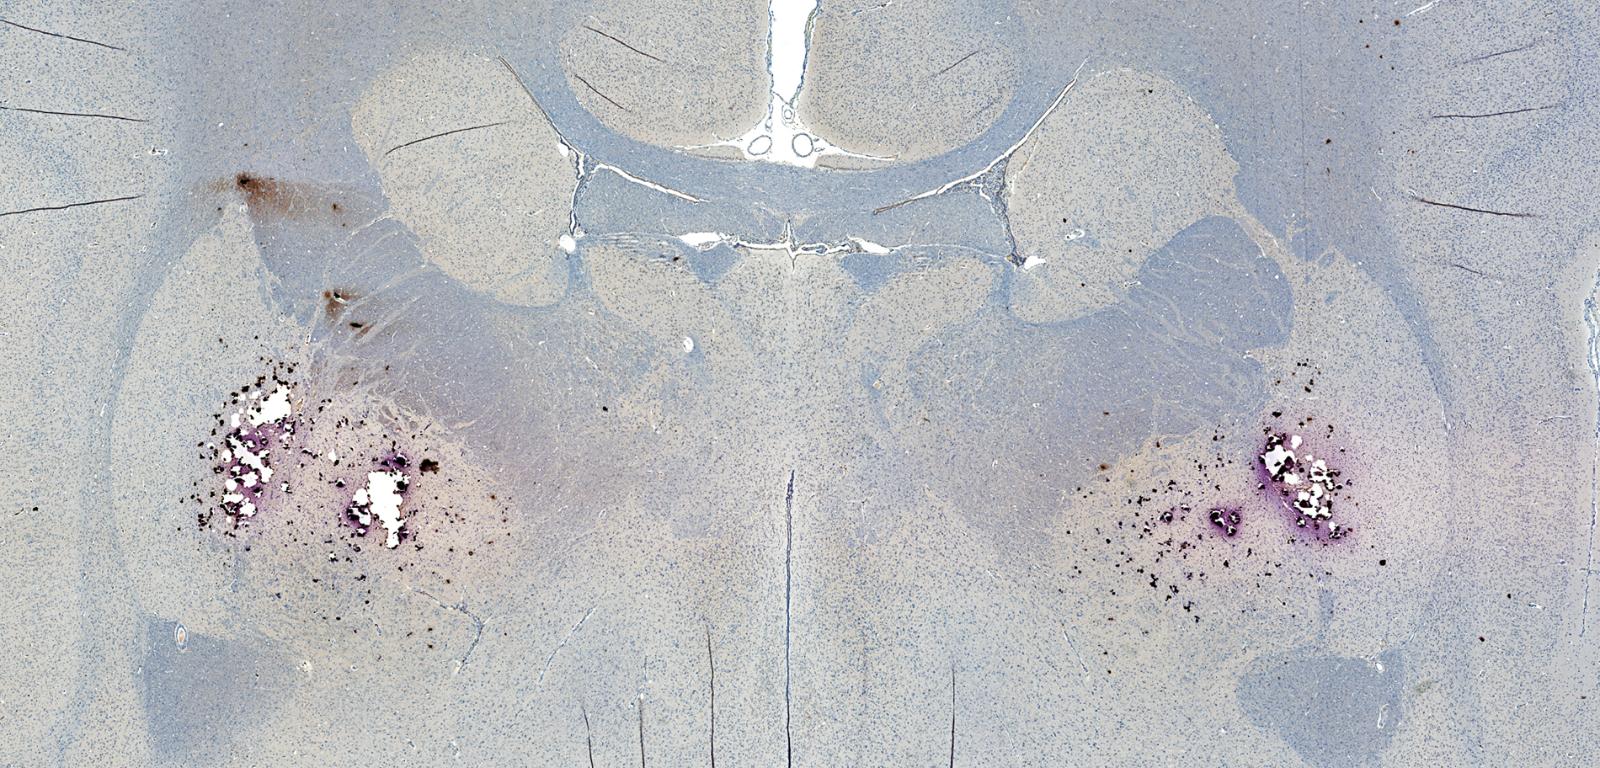

Beta-amyloid w mózgu. Beta-amyloid w mózgu. Shutterstock

Jednym z kluczowych symptomów tej choroby jest gromadzenie się w mózgu szkodliwych złogów białka, czyli beta-amyloidu. Do tej pory za jego głównych producentów uważane były neurony. Publikacja w „PLOS Biology” podważa to przekonanie.

Zespół naukowców z University College London stwierdził, że beta-amyloid mogą wytwarzać również oligodendrocyty. Są to komórki glejowe, które w zdrowym mózgu odpowiadają przede wszystkim za tworzenie osłonek mielinowych wokół aksonów neuronów, usprawniając w ten sposób przewodzenie impulsów nerwowych. Nie tylko posiadają wszystkie niezbędne składniki do produkcji beta-amyloidu, ale w warunkach laboratoryjnych mogą wytwarzać go nawet więcej niż neurony. Ponadto powstające dzięki nim białko wykazuje silniejszą tendencję do tworzenia toksycznych złogów.